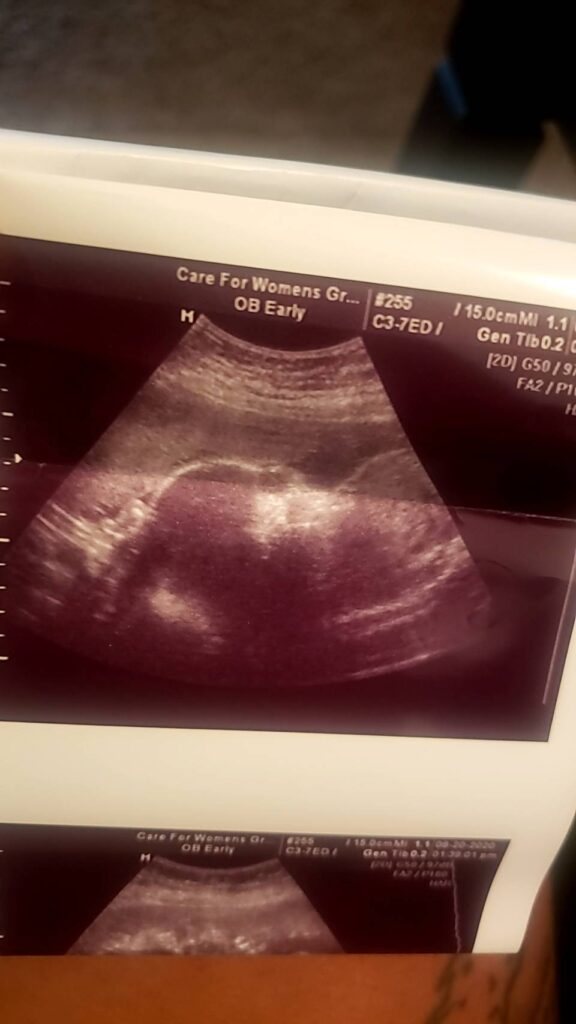

雙胞胎超音波紀錄 : 27週 Posted on August 25, 2020 by yourtesttubebaby 27週的雙胞胎寶寶就是長這樣的! 哇,再十週就要報到啦!!!🎉🎉🎉 ↑↑↑(圖一) 照出其中一位寶寶的臉與眼睛 ↑↑↑(圖二) 兩個寶寶頭與頭相靠相依 ☀ 網站上每位小寶貝都是我們的成功案例,照片皆經父母親許可使用 ( 若未經允許請勿轉載 ) ☀ Posted in Uncategorized